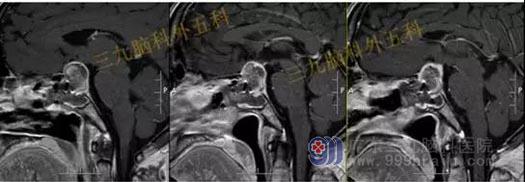

术前头部MR检查结果:鞍区示一团块状占位性病变,T1WI呈略低信号,T2WI呈稍高信号,增强后呈明显强化,病变界限清晰,边缘光整,范围约为3.1cm×2.7cm×2.0cm。病变示明显束腰征,垂体柄及视交叉受压显示不清,邻近颈内动脉受压移位,部分被包绕。

结果:鞍区垂体大腺瘤;病变部分包绕邻近颈内动脉。

手术过程:内镜下经鼻蝶鞍区垂体大腺瘤切除术,术中磨除鞍底,先行瘤内减压,双吸引器有序切除肿瘤,垂体及鞍隔保护良好,无脑脊液漏形成,肿瘤全切。

术后头部MR检查提示:肿瘤已全切。